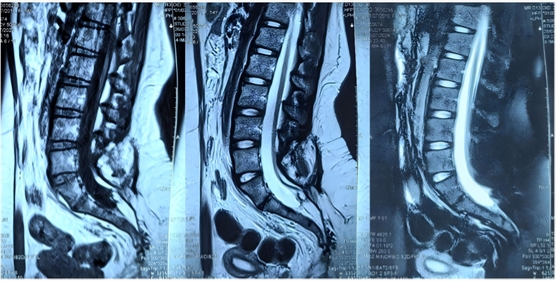

患者,女,15歲,出生后即發(fā)現(xiàn)腰骶部偏左側(cè)包塊,兩側(cè)臀部不對(duì)稱(chēng),11個(gè)月時(shí)發(fā)現(xiàn)包塊增大,考慮為脊髓拴系、脊髓脂肪瘤。2歲左右出現(xiàn)排尿費(fèi)力、尿失禁(伴尿床),遂于某兒童醫(yī)院接受脊髓拴系松解術(shù)。術(shù)后二便功能障礙進(jìn)行性加重,且出現(xiàn)下肢畸形,1年前復(fù)查發(fā)現(xiàn)脊髓拴系術(shù)后復(fù)發(fā)(圖一),遂于我科行二次松解手術(shù)。術(shù)后病情穩(wěn)定(圖二),未再有加重趨勢(shì),仍遺留大小便失禁,表現(xiàn)為小便漏尿,伴有排尿費(fèi)力,且小便都是滴出,自己不能感知。大便干燥便秘,至少三四天一次大便,大便費(fèi)力,稀的時(shí)候失禁。

圖1為1年前脊髓拴系松解術(shù)前磁共振檢查片子